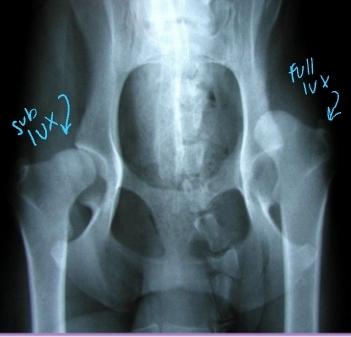

Screening for Hip Displasia

OFA: Evaluates passive laxity

When: Certified >2 years

Grades:

Normal: excellent, good, fair, borderline

Dysplastic: mild, moderate, severe

PennHip: Evaluates passive distractive laxity

When: Certified >16 weeks

Grades: Scale 0–1

0.58 = 58% femoral head displacement

Diagnostic Imaging for Hip Dysplasia

VD most useful

Want >50% acetabular coverage!

Rads: Bone shape, remodeling, osteophytosis(neck), enthesiophytosis (Morgan’s line), laxity

Do not treat the radiograph!

CT + MRI: not useful and expensive

Arthrocentesis: Rule out infection or neoplasia

Arthroscopy: Articular lesion evaluation, prior to TPO

Rarely needed

Hip Luxation Pathophysiology

Et: Results from failure or tear of Joint capsule or Round ligament

Most common joint luxation in dogs

Types:

Craniodorsal (#1): hit-by-car or blunt trauma

Caudoventral: fall with abduction

Hip Luxation Diagnosis

Cs: Crepitus, pain, shortened limb length(craniodorsal), pelvic asymmetry

Palpate: Iliac crest(wing), Greater trochanter of femur, and Ischiatic tuberosity form a straight line

Normal = shallow triangle

Thumb test: Place thumb in ischiatic notch and externally rotate limb

Normal = Thumb should be pushed out of notch

Radiographs: lateral & VD